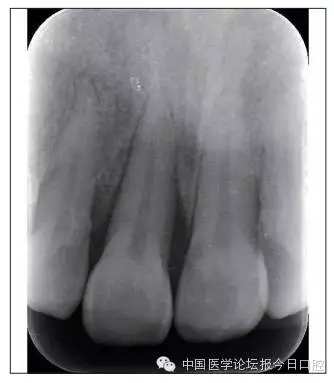

矯治后,牙列間隙關(guān)閉,面型及覆(牙合)覆蓋改善。11根尖片(圖8)顯示,治療后較治療前,牙周支持組織增加,牙槽骨角形吸收區(qū)水平向縮小0.3mm,垂直向縮小0.6mm。11松動(dòng)Ⅰ度,余切牙無(wú)松動(dòng)。

圖8 治療后根尖片

本病例右上中切牙牙槽骨角形吸收,在盡量保證治療前后根尖片投照角度一致的情況下,以鄰牙作為校準(zhǔn),在根尖片上對(duì)治療前后的骨量進(jìn)行評(píng)價(jià),治療后牙槽骨角形吸收區(qū)水平向縮小0.3 mm,垂直向縮小0.6mm。盡管根尖片并不能說(shuō)明骨量改變,但從影像學(xué)上能看到骨吸收區(qū)域有所減小。